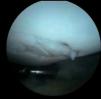

Figura 2 Artroscòpia. Cossos lliures articulars en recessió articular interna.

Es practica una artroscòpia, en la qual s'observen (figs. 2, 4, 6-8):

• Múltiples fragments condrals lliures de vores agudes, que s'identifiquen com recents, i de vores rodones que es cataloguen com antics.

• Lesió condral anfractuosa extensa, amb fragments inestables en cres-ta de la ròtula i en faceta externa, de grau III.

• Resta d'estructures intraarticulars íntegres.

• Es procedeix a l'exèresi dels cossos lliures i la regularització de la lesió condral seguida d'estabilització per vaporització.